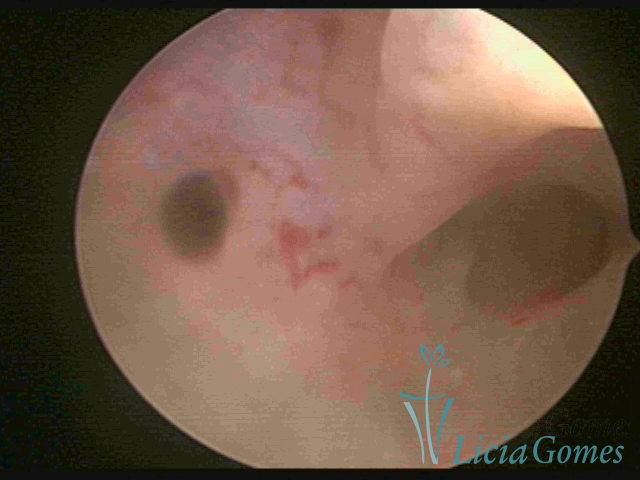

ADENOMIOSE

É a presença de tecido endometrial na camada muscular do útero

A vídeo-histeroscopia permite diagnosticar às lesões próximas às camadas miometriais superficiais, próximo ao endométrio visualizando lesões de coloração violácea, circunscritas, ou acastanhadas com conteúdo achocolatado.